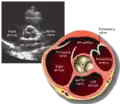

A transthoracic echocardiogram (TTE) is the most common type of echocardiogram, which is a still or moving image of the internal parts of the heart using ultrasound. In this case, the probe (or ultrasonic transducer) is placed on the chest or abdomen of the subject to get various views of the heart. It is used as a non-invasive assessment of the overall health of the heart, including a patient's heart valves and degree of heart muscle contraction (an indicator of the ejection fraction). The images are displayed on a monitor for real-time viewing and then recorded.

A TTE is a clinical tool to evaluate the structure and function of the heart. All four chambers and all four valves can be assessed by TTE, but the quality and visibility of these structures varies from person to person. Other structures visible on TTE include the aorta, the pericardium, pleural effusions, ascites, and inferior vena cava. It can be used to diagnose a heart attack, enlargement/hypertrophy of the heart, infiltration of the heart from an abnormal substance (e.g. amyloidosis). Weakness of the heart, and cardiac tumors. With advanced measurements of the movement of the tissue with time (Tissue Doppler), it can measure diastolic function, fluid status,[1] and ventricular dyssynchrony.

This view is obtained in the same window as the parasternal long, but with the probe rotated 90°. In this view, the aortic valve is seen in cross-section with the right ventricular inflow & outflow tracts visible with the tricuspid valve as well. Pulmonary valve is not visible in this view. Both the right and left atria are visible.

The standard PSAX view is at the level of the aortic valve, but moving the probe along the long-axis can review the LV outflow tract, LV at the base, and LV at the midsection.

Structures visible:

- Aortic valve in short-axis

- Aortic valve dysfunction, aortic sclerosis/stenosis

- Tricuspid valve in long-axis

- Pulmonary valve in long-axis

- Right ventricle, including inflow and outflow tracts

- Left ventricle in short-axis